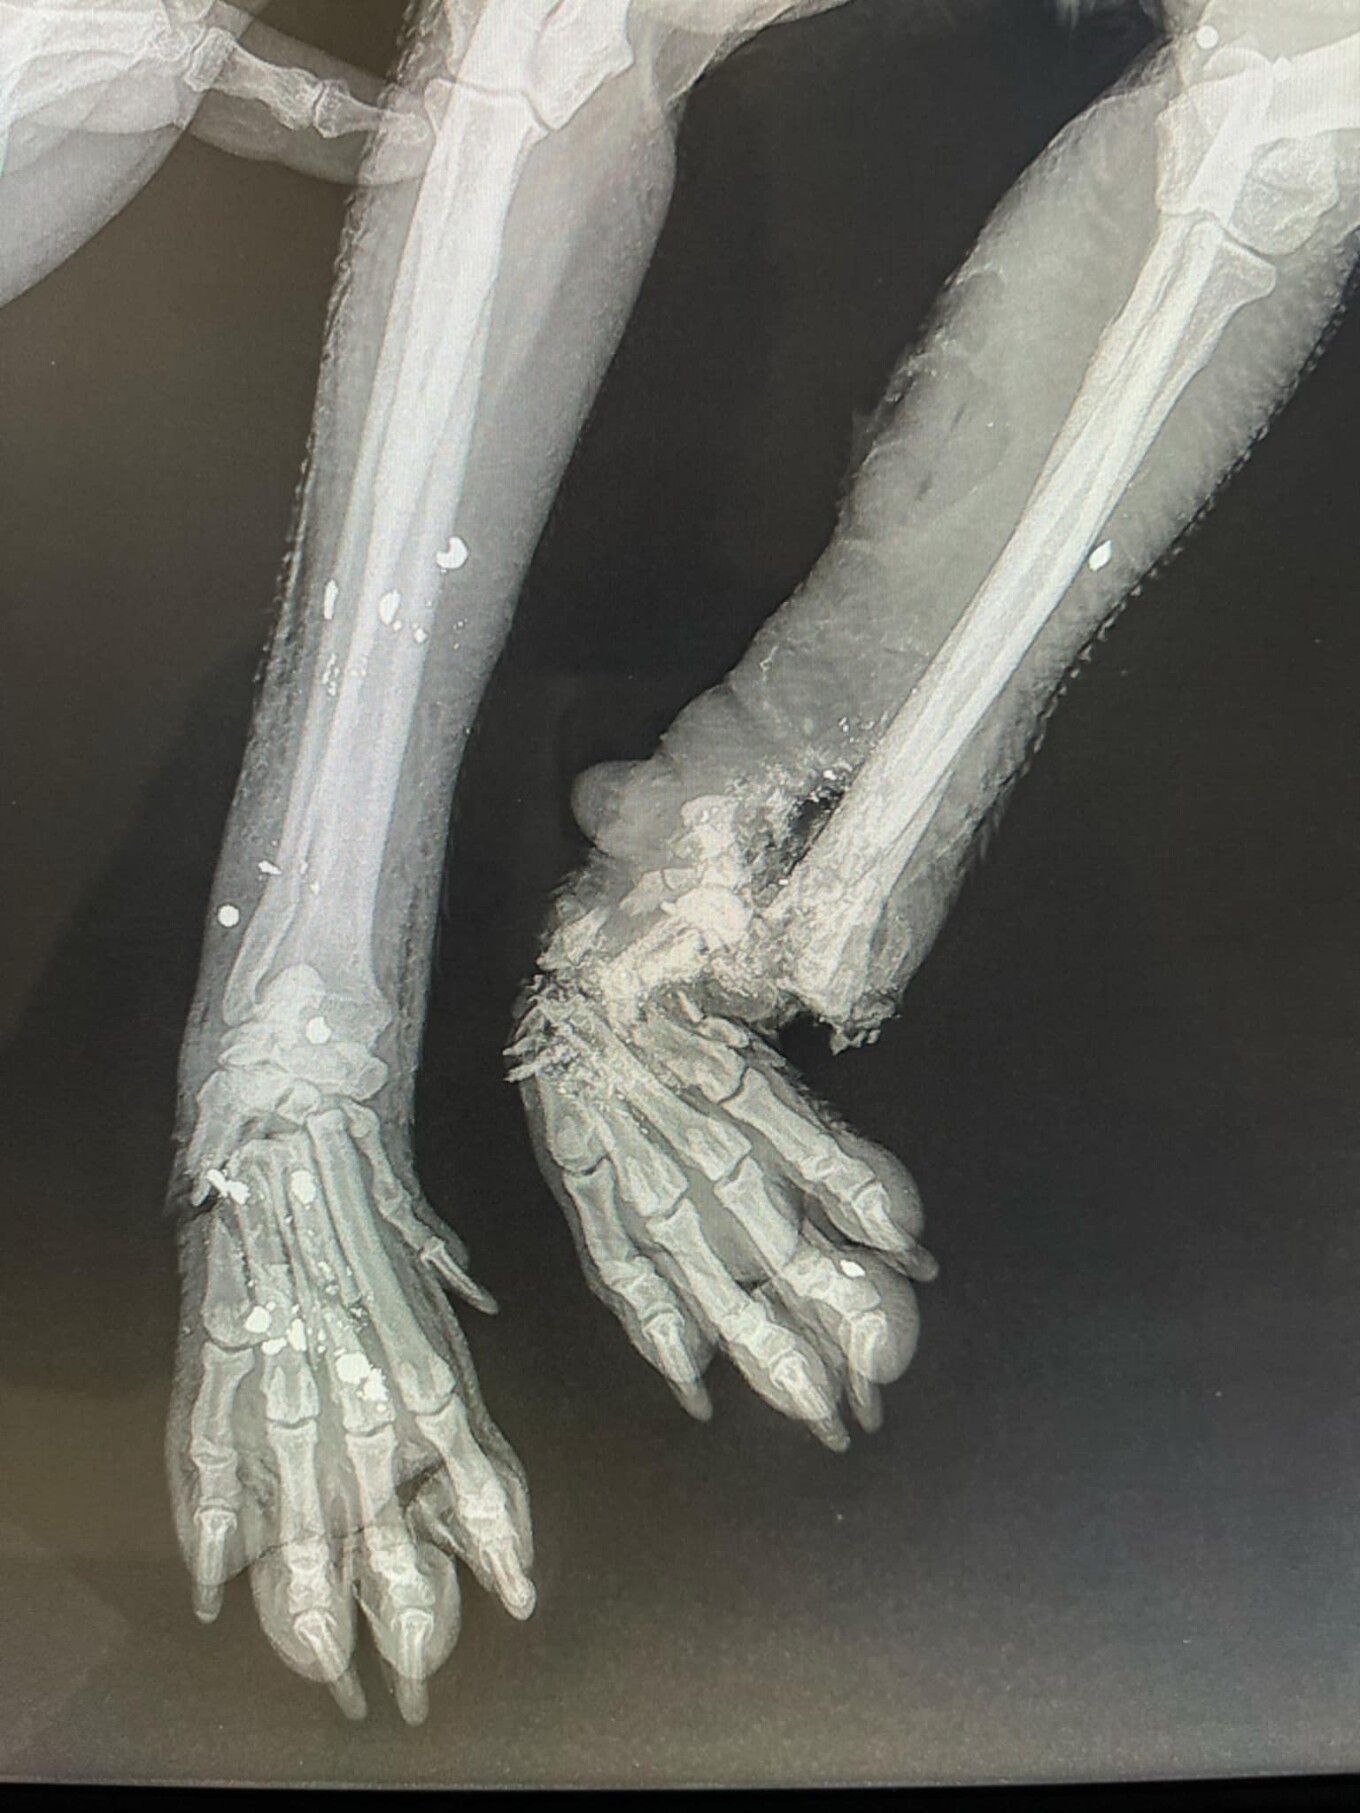

Όπως αναφέρει ο ιστότοπος flashnews.gr, η μικρόσωμη σκυλίτσα, βρέθηκε σοβαρά χτυπημένη, με τα κόκκαλα στο ένα της πόδι να είναι κυριολεκτικά θρυμματισμένα, ενώ στο άλλο πόδι το κόκκαλο φαίνεται εκτεθειμένο.

Παράλληλα, στο σώμα της βρέθηκαν και σκάγια, τα οποία επιβεβαιώνουν πυροβολισμό.